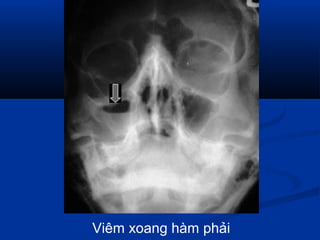

 Viêm xoangViêm xoang

Viêm xoang hàm phải